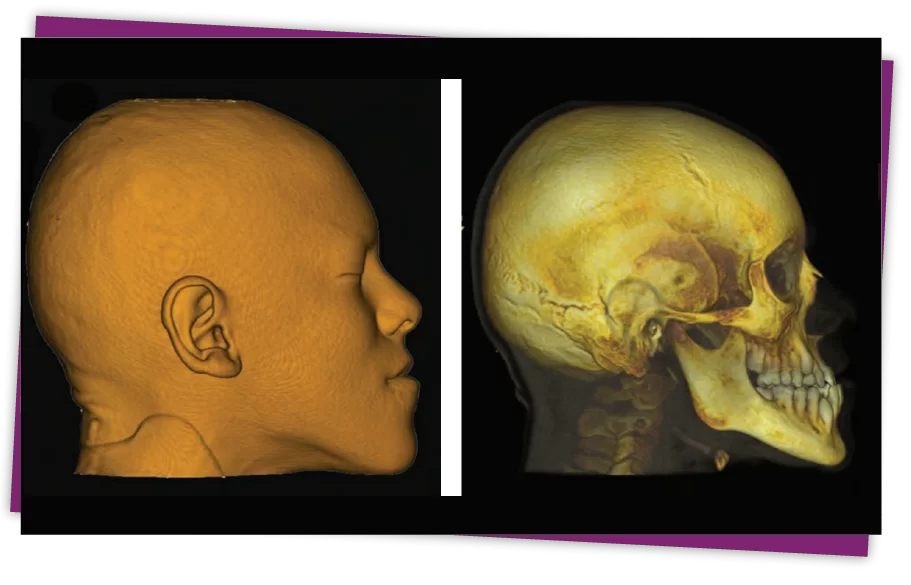

Đặc điểm này rất dễ nhận ra khi quan sát bằng mắt thường nhưng để xác định một cách chính xác tình trạng móm của bạn là do đâu thì nên đến trực tiếp nha khoa để các bác sĩ đo đạc, chụp phim CT scan toàn sọ mặt cũng như thực hiện một số phân tích khác để từ đó mới biết tỷ lệ móm như thế nào.

Từ những thông số đó, bác sĩ mới đưa ra quyết định nên điều trị móm bằng cách niềng răng, bọc răng sứ hay phải phẫu thuật chỉnh móm.

Bước 2: Tiến hành chụp CT scan từ đó xác định nguyên nhân, đánh giá và đề ra các phương pháp điều trị phù hợp cho khách hàng